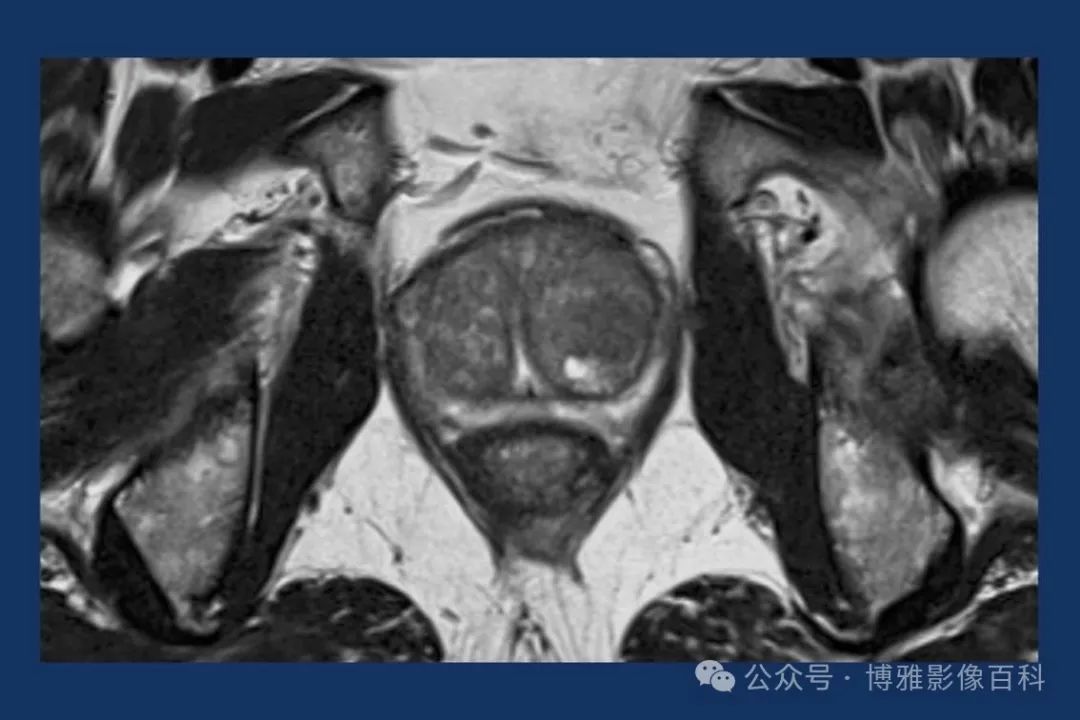

MR 解剖学

前列腺良性增生患者的轴向T2 图像,其他方面正常。外周带是一薄层均匀的高信号,边界清晰连续性的低信号包膜。移行带通常表现为不均匀中等信号,病灶被边界清楚的BPH良性前列腺增生结节所取代。精囊具有均匀T2高信号。未见淋巴结肿大。